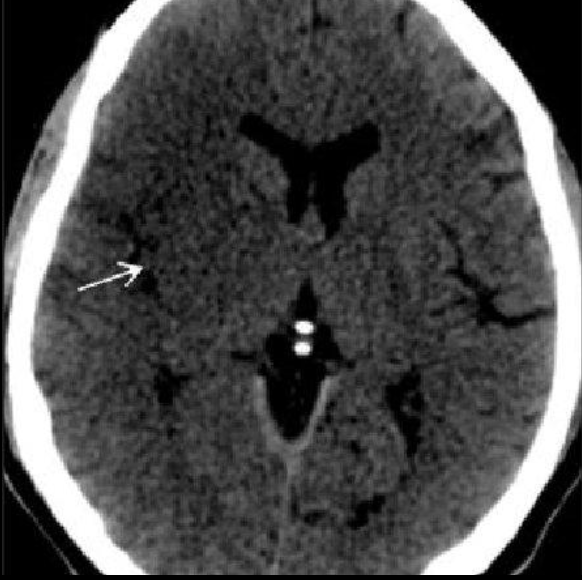

EVC isquémico

Fase aguda